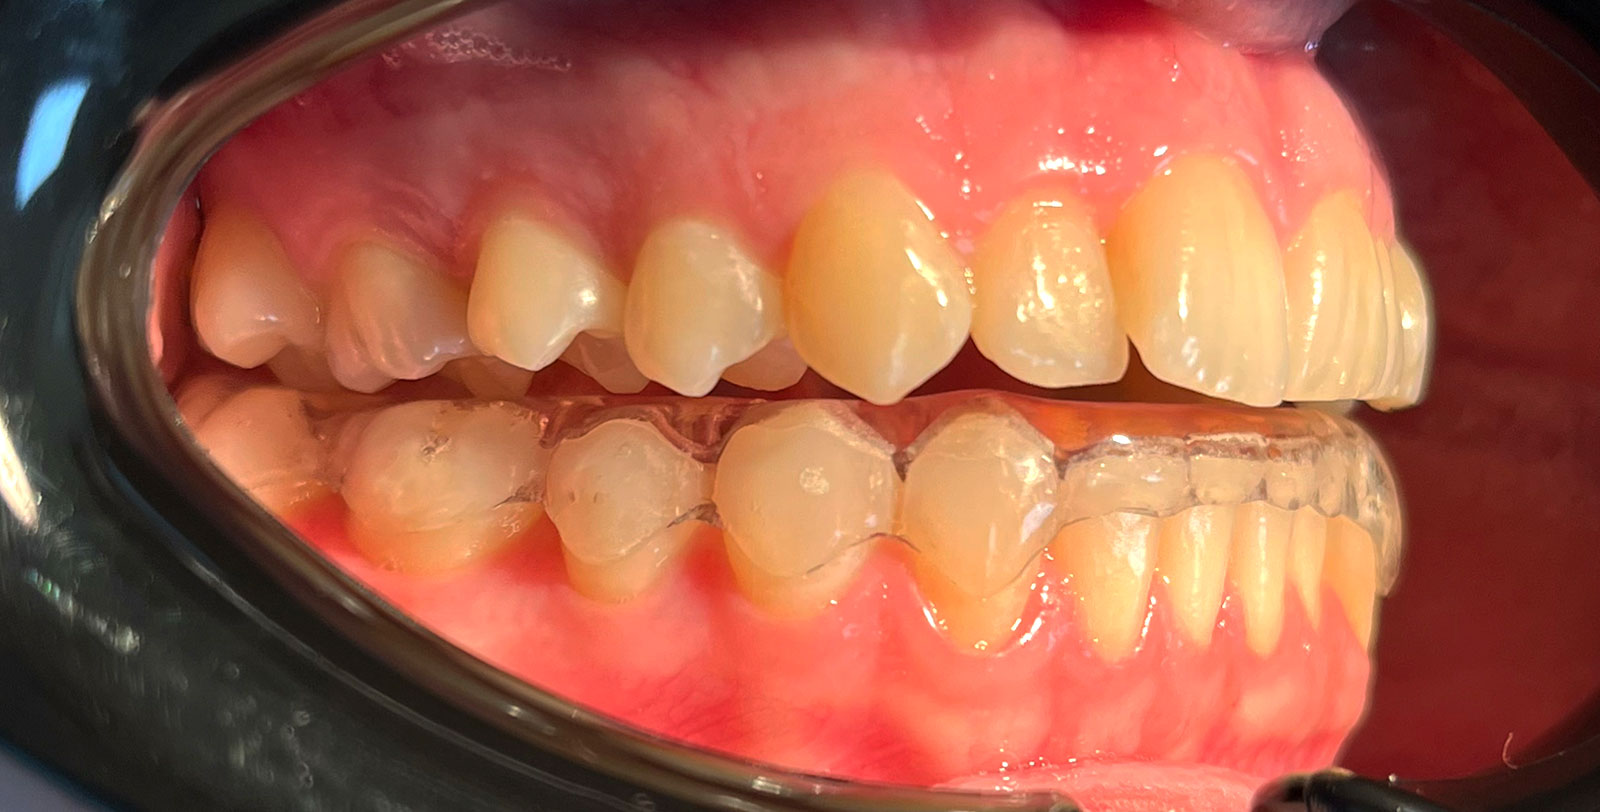

- Застосування міорелаксуючих кап сплінт-шини, які допомагають знизити навантаження нижньощелепного суглоба і запобігають скреготу зубів (бруксизм).